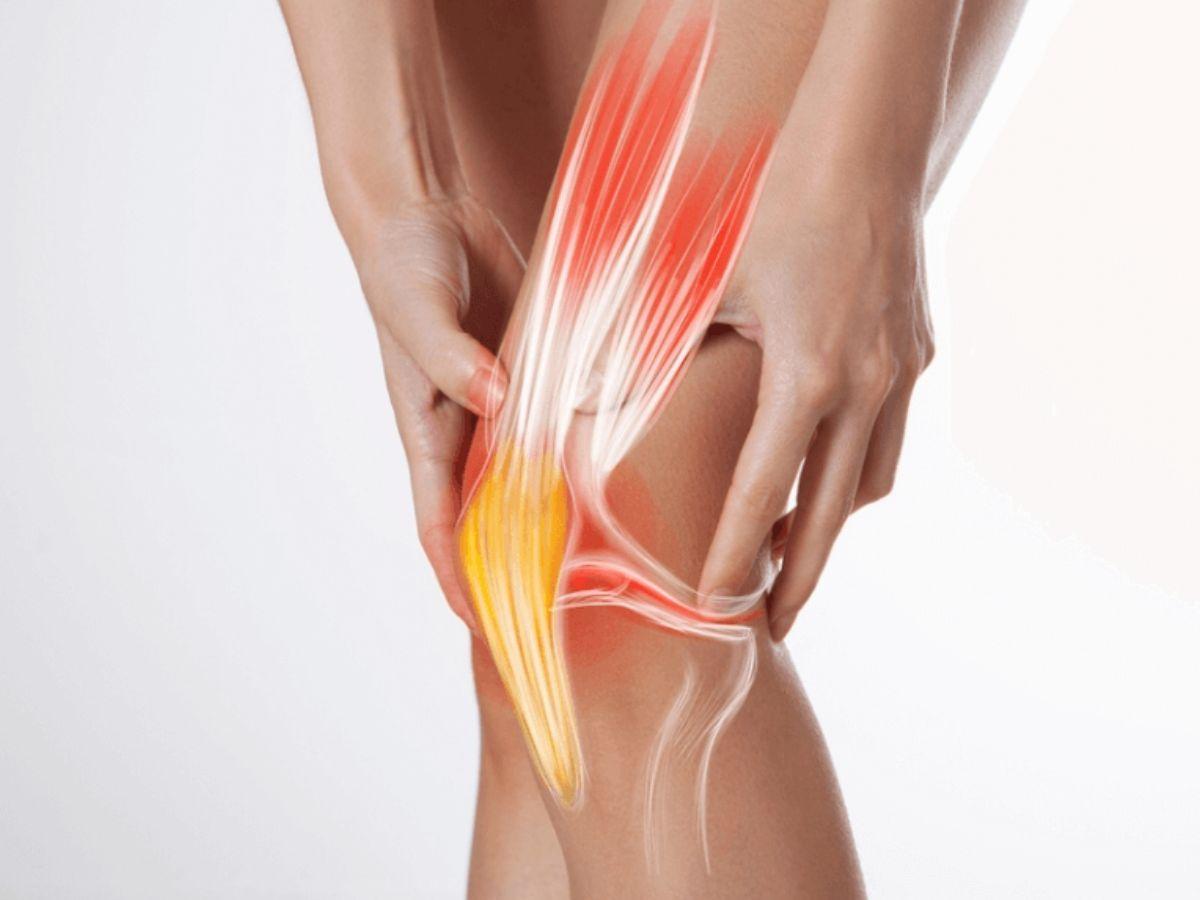

Gân cơ: Ở khu vực khớp gối có rất nhiều gân cơ với chức năng khác nhau như cơ tứ đầu, cơ bánh chè, gân cơ kheo và gân dải chậu chày.

Dây chằng: Khớp gối có bốn hệ dây chằng chính gồm dây chằng chéo trước, dây chằng chéo sau, dây chằng trong bên chày và dây chằng ngoài bên mác. Hệ thống dây chằng này giúp giữ vững hệ cơ khớp, liên kết và cố định cấu trúc chân. Đây cũng là bộ phận dễ bị tổn thương nhất khi vận động.

Hội chứng dải chậu chày

Hội chứng dải chậu chày là tình trạng viêm khớp dải chậu chày do vận động quá thường xuyên nhưchạy bộ hoặc căng thẳng thần kinh. Triệu chứng ban đầu là cảm giác đau bên ngoài khớp, có cảm giác đau đớn hơn khi co gập chân hoặc di chuyển đường dài. Cơn đau tăng dần khi vận động mạnh và có thể đau lan lên khu vực hông và xương chậu.